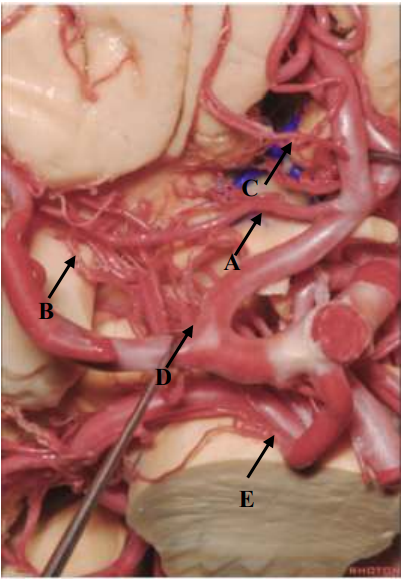

Qual seta aponta para a Artéria Recorrente de Heubner?